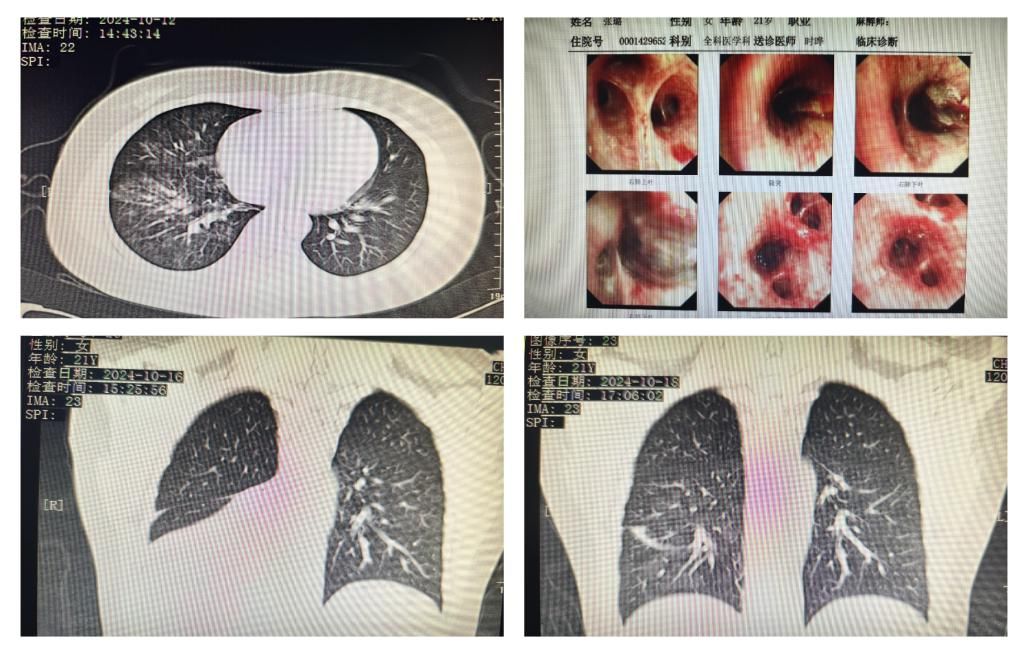

。门诊电子喉镜检查未见明显异常,胸部CT提示右肺中下叶炎症,以“未分化疾病-咯血原因待查”入住全科医学科。患者4年前诊断克罗恩病,长期应用免疫抑制剂英夫利昔单抗治疗。入院经抗感染、止血治疗,患者仍有间断咯血,伴一过性呼吸困难及血氧饱和度降低,时晔、徐博主任团队详细询问病史及认真阅片,患者影像学特点及感染相关指标正常,不支持一般感染性肺炎的诊断,安排第三天复查胸部CT,发现右肺下叶肺不张。结合发病时情况及支气管解剖特点,高度怀疑气管吸入异物,病情紧急,需要尽快支气管镜检查明确右下肺不张病因。此时已临近下班,郭伟主任恰好在病房,及时联系呼吸与危重症一科陈瑞琳主任医师进行会诊,指导值班医生行次日支气管镜检查准备,并和家属充分知情告知检查必要性及可能风险。

次日,在时晔主任及雷鸣主管医生陪同下,陈瑞琳主任医师进行支气管镜检查,发现患者右肺下叶管口条索状异物,完全阻塞右肺下叶支气管,活检时发现异物质软,且与气道壁嵌合,反复使用活检钳及异物篮均不能顺利取出。患者因治疗时间长剧烈咳嗽、不耐受治疗,随急诊请胸外科戴云副主任医师、麻醉科徐瑞芬主任医师到支气管室会诊配合,经过液氮冷冻、网篮及反复抽吸后,取出数条支气管树状异物,似为牛油果泥与凝血块混合物,此时右肺下叶管腔完全通畅。术后次日复查胸部CT,患者右下肺不张明显改善,继续药物抗感染止血等治疗,患者病情好转,未再咳血,双肺呼吸音正常,血氧饱和度99%,于10月21日顺利出院。